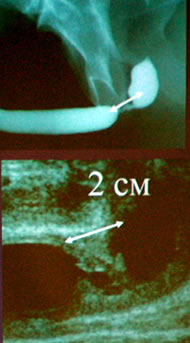

"Новые технологии в лечении стриктур уретры"

Конец в конец